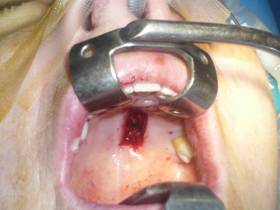

Hard palate graft